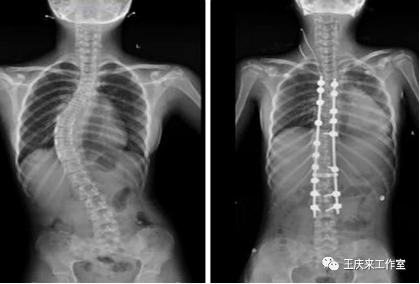

(3)重度:cobb角>45°,病情進(jìn)展迅速者可能就要考慮手術(shù)矯正治療。